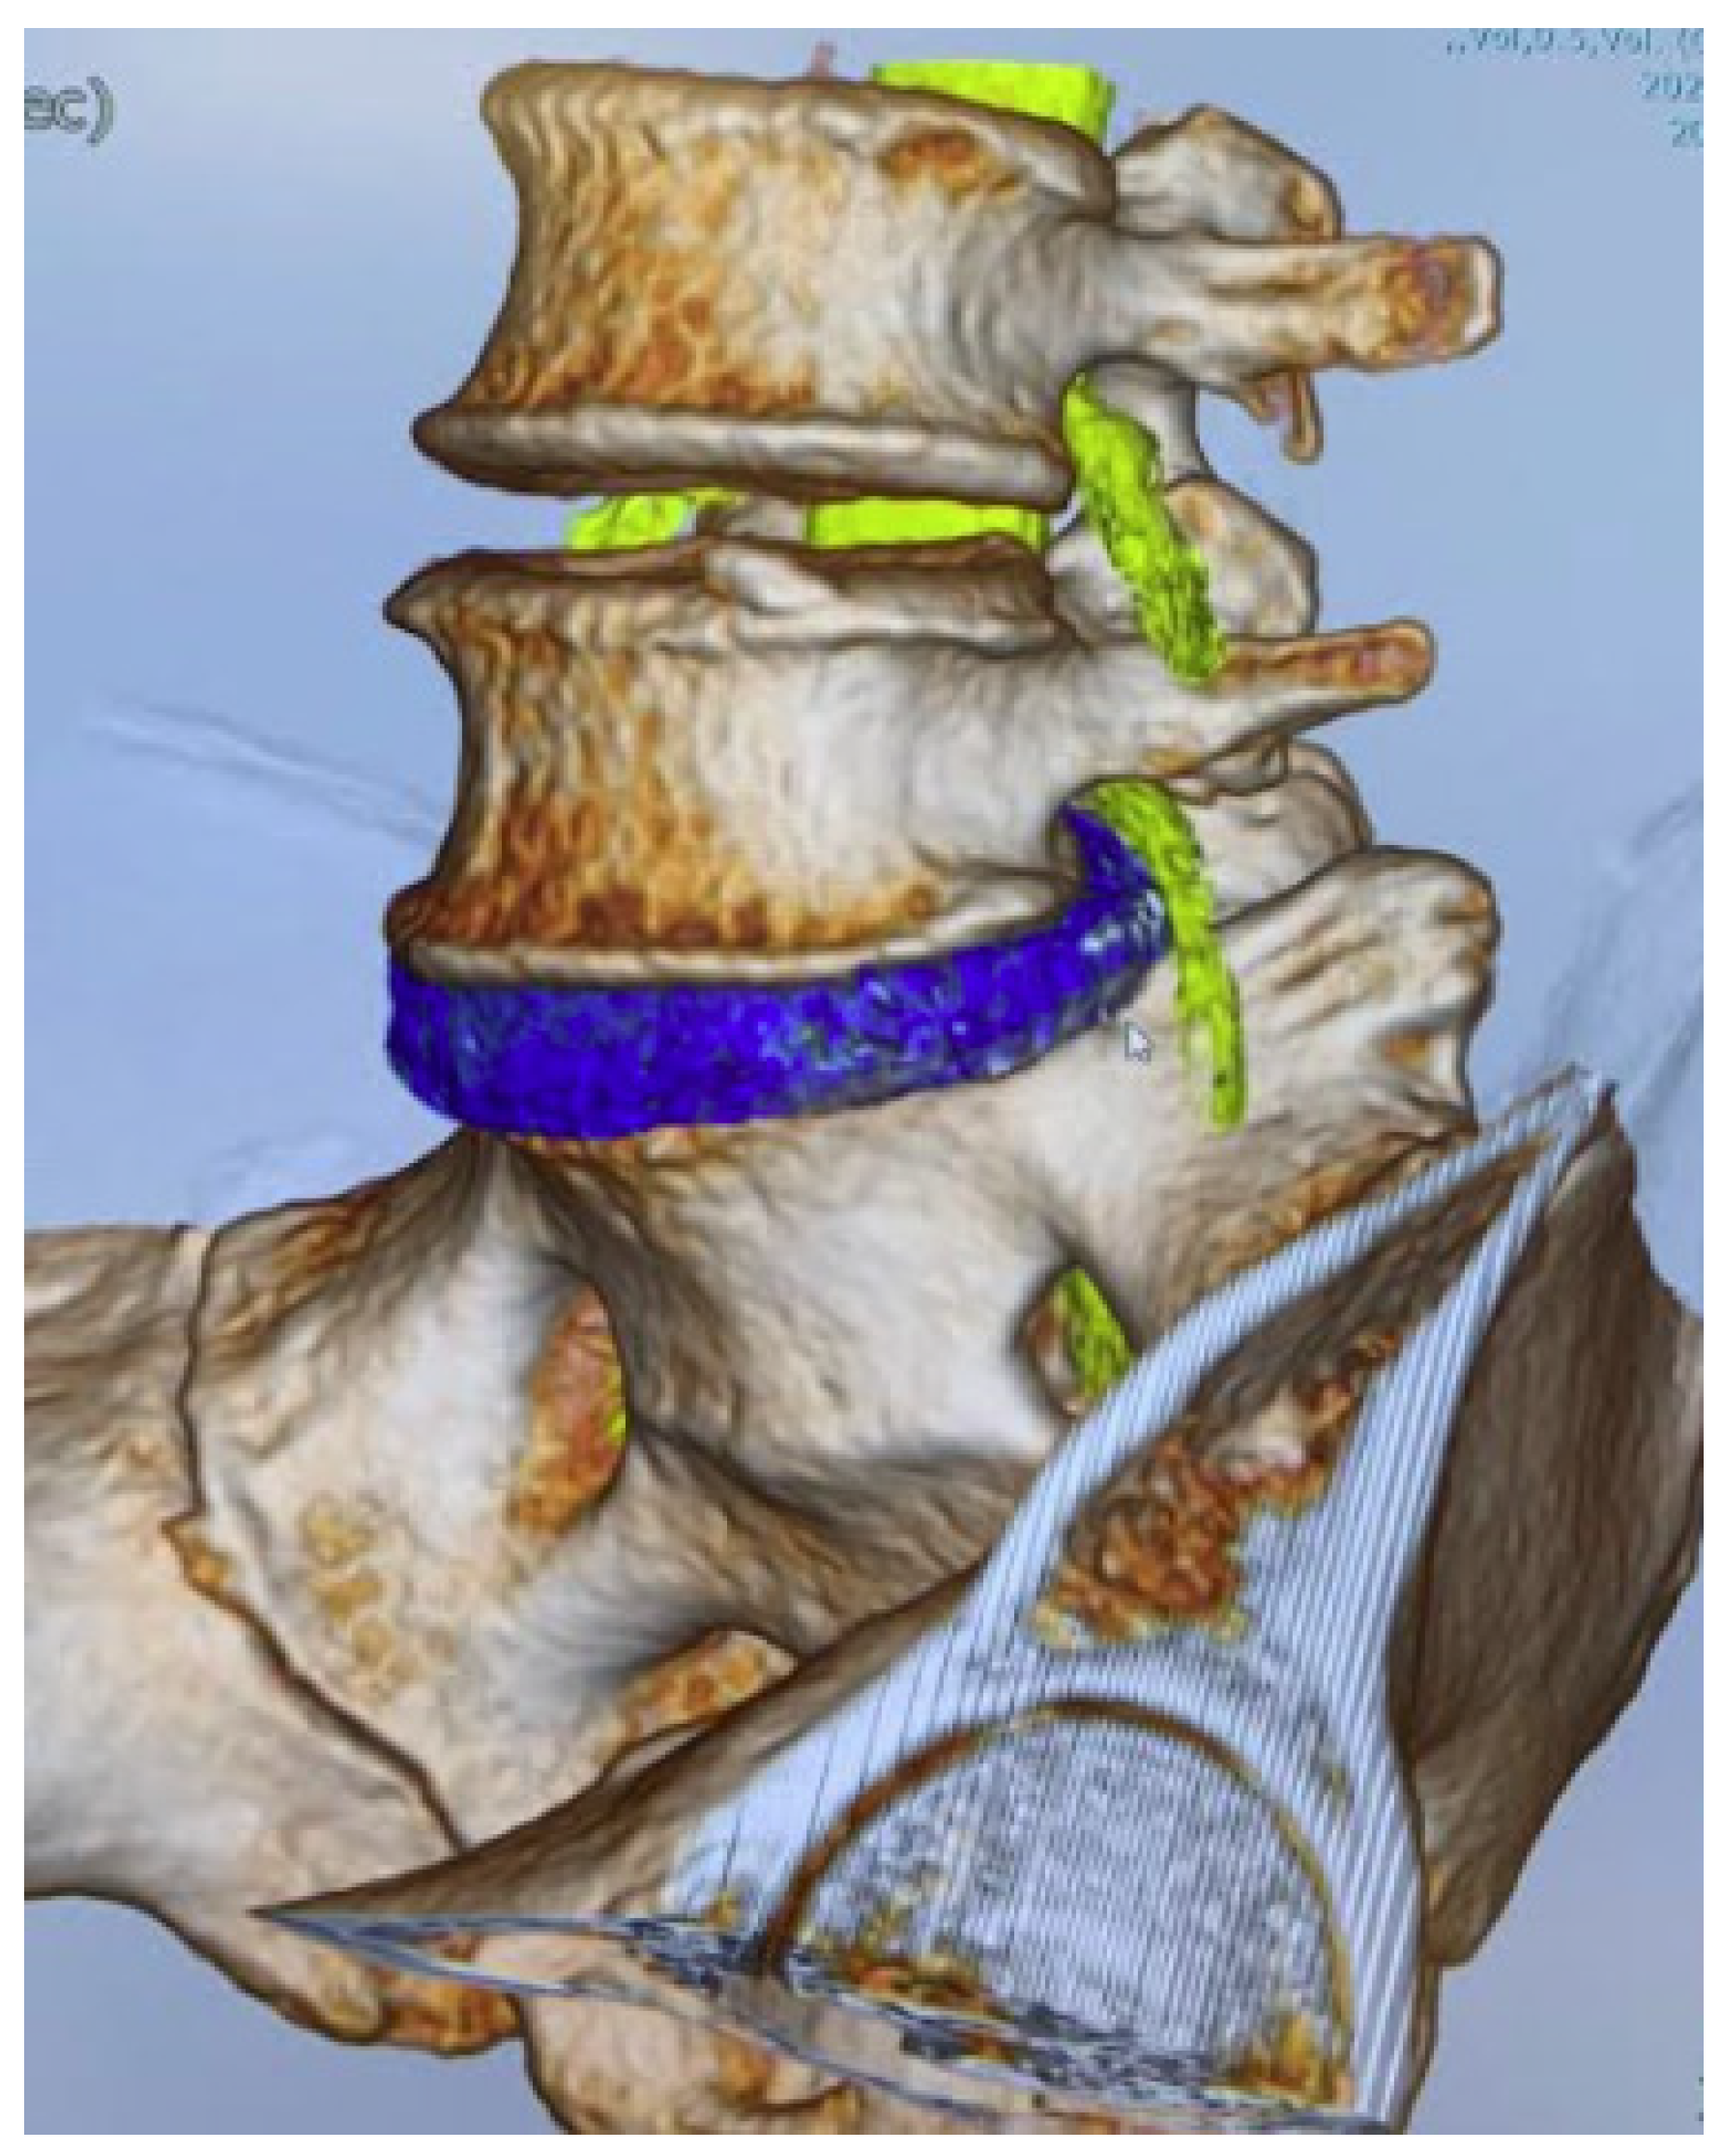

All herniated discs were visualized in the fusion images, and the root compression site was clearly demonstrated in foraminal/extraforaminal disc herniations (Figure 6, Figure 7 and Figure 8).

Figure 6.

A 46-year-old male, left L5/S1 foraminal/extraforaminal disc herniation. (A): Anterior view. (B): Posterior view. (C): Lateral view. (D): Without bony structure.

Figure 7.

A 46-year-old male, left L5/S1 foraminal/extraforaminal disc herniation. (A): Anterior view. (B): Lateral view. (C): Anterior oblique view. (D): Posterior oblique view.